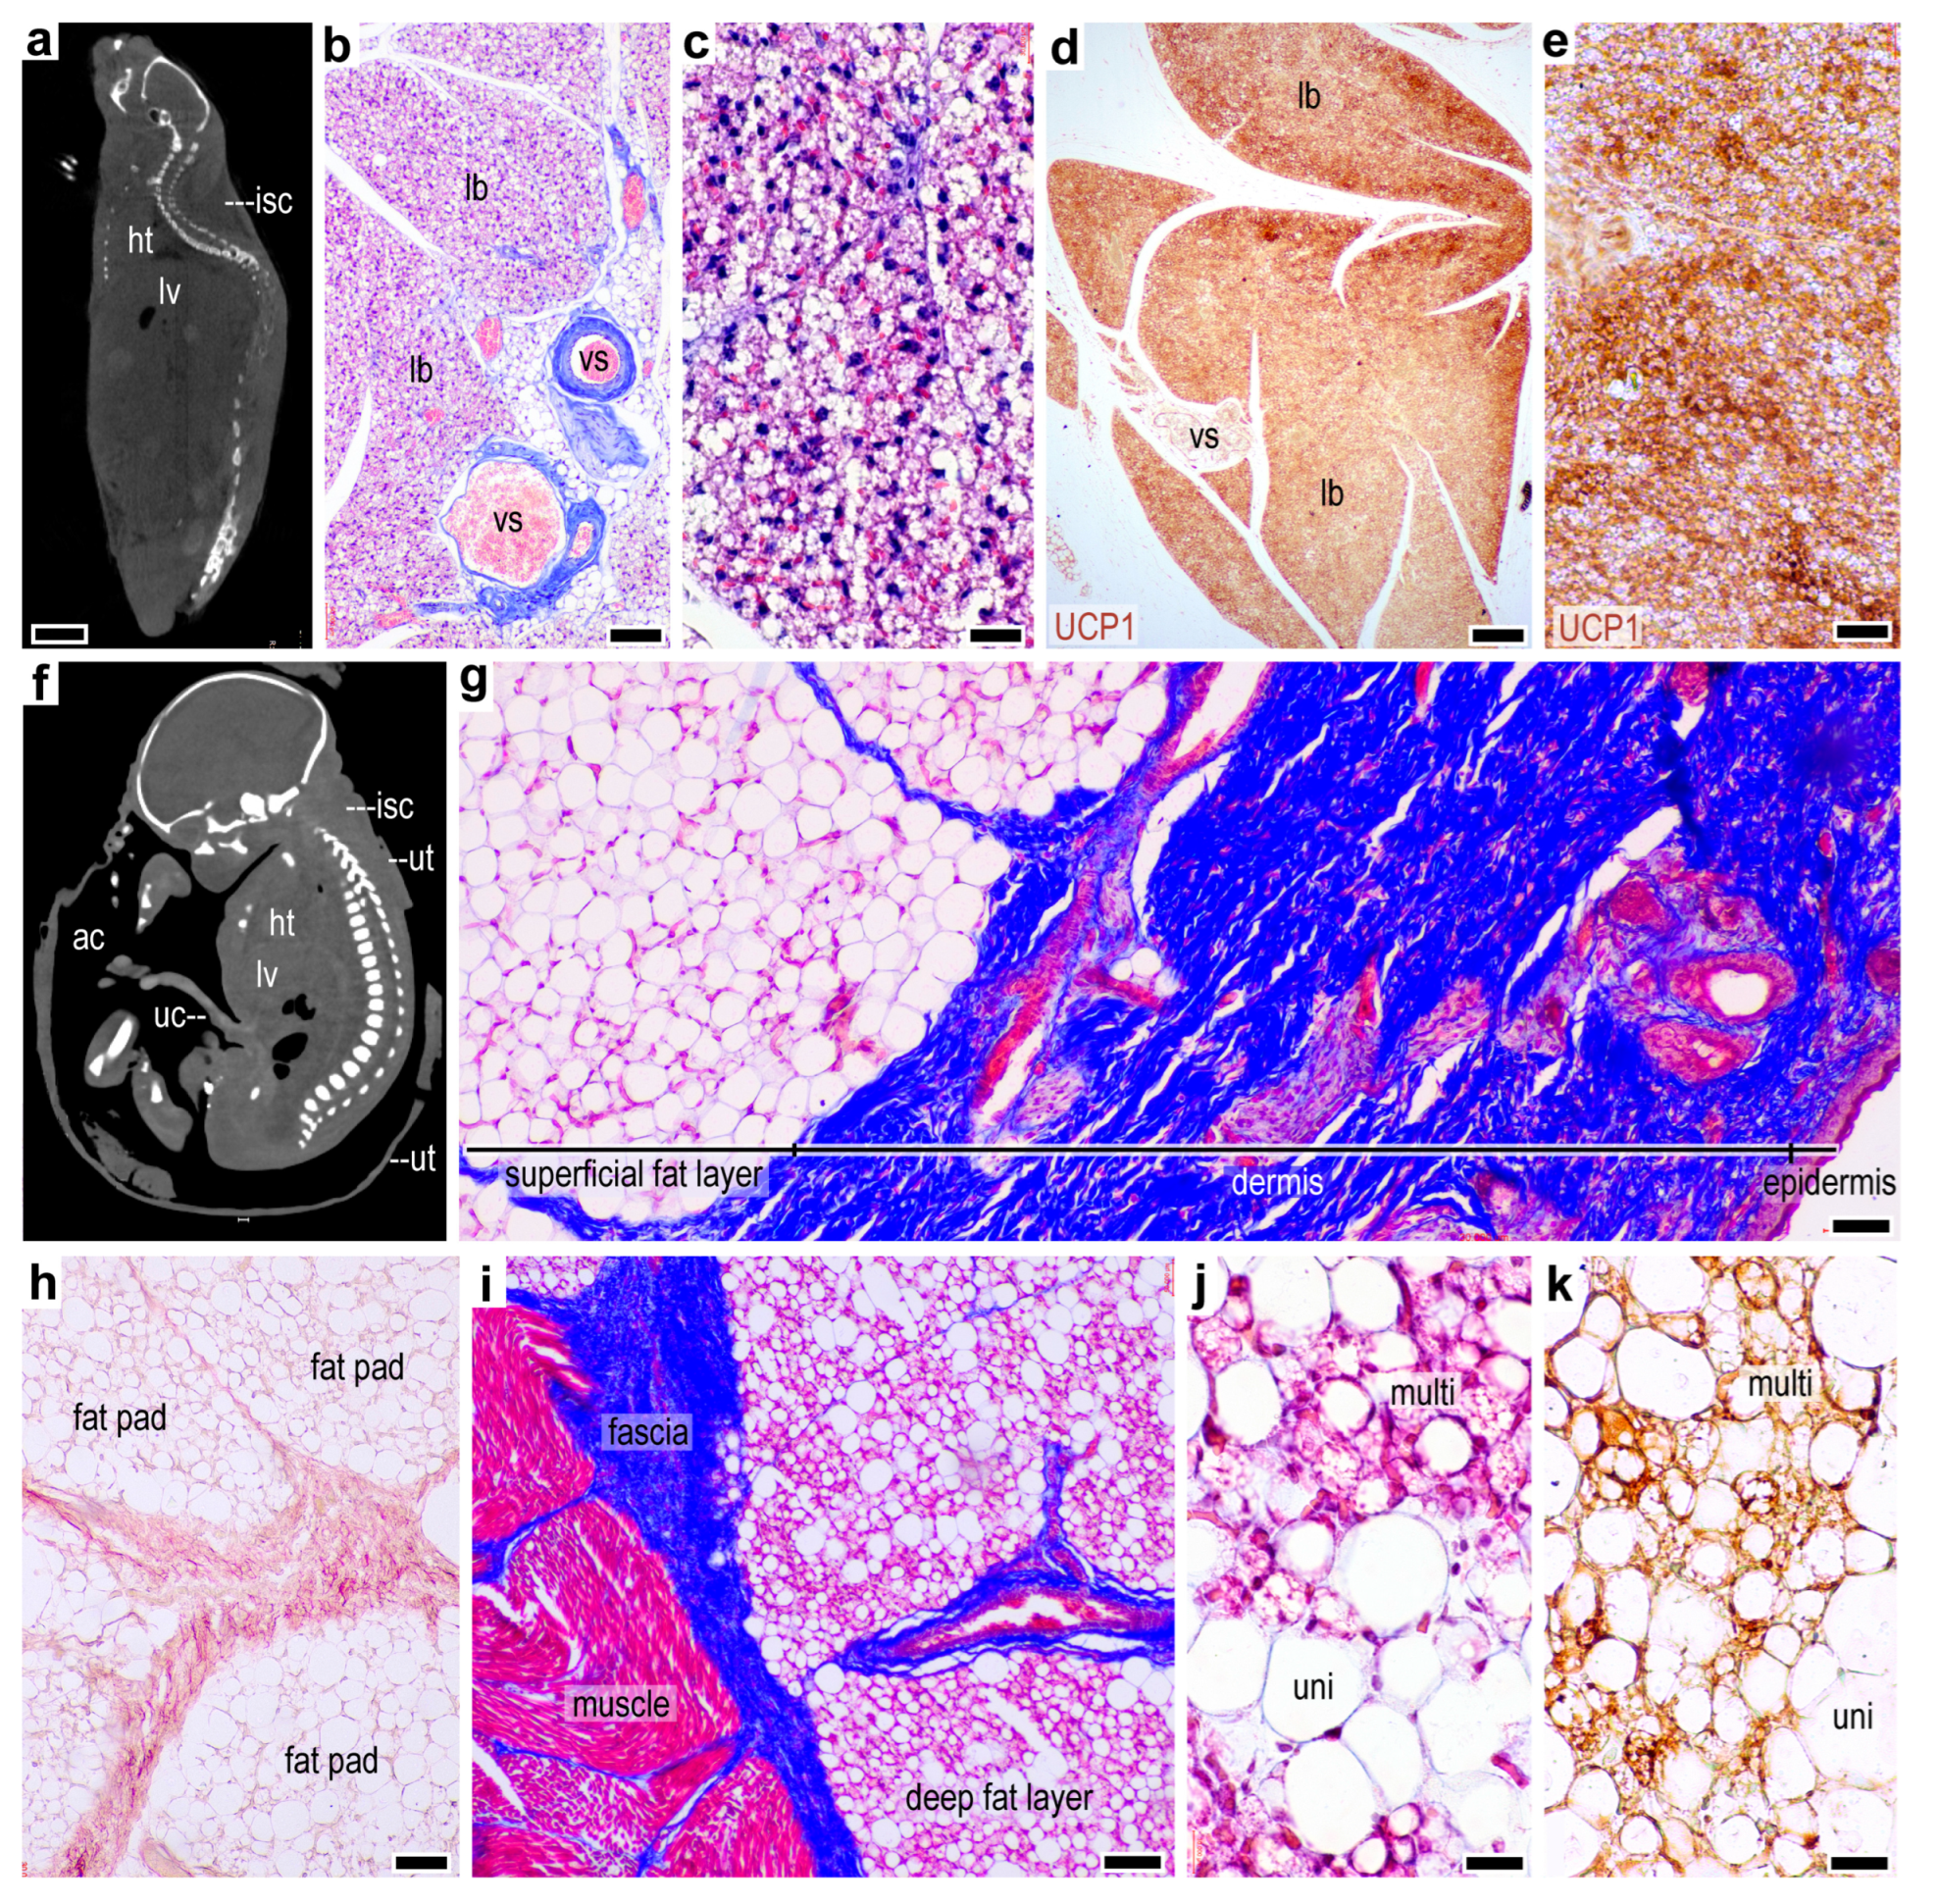

2.1. Lack of a Thermogenic Interscapular Fat Depot in Human

2.2. Subcutaneous Thermogenic Fat in the Abdominal Region